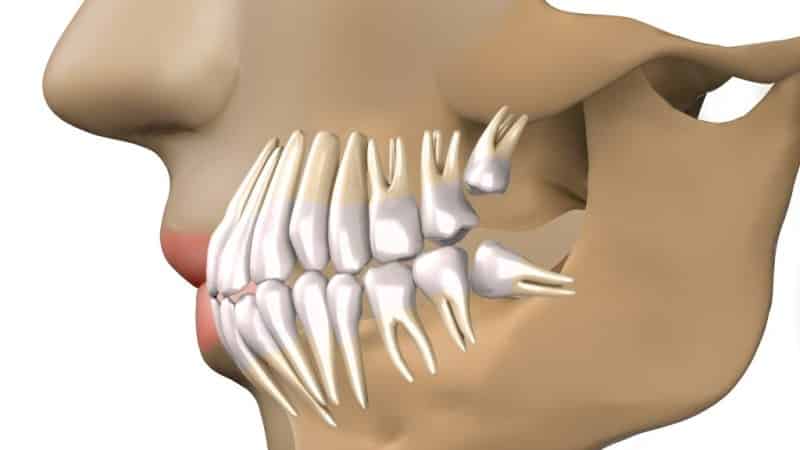

Когда все зубы уже выросли, «восьмерки» могут начать прорезываться, но часто для них нет места. В таких случаях они могут расти в неправильном направлении, повреждая корни соседних зубов. Стоматолог может рекомендовать удаление зуба. Прежде чем принять такое решение, необходимо провести тщательное исследование полости рта с использованием рентгена.

- Дистопию, которая характеризуется горизонтальным расположением зуба мудрости в зубной лунке, препятствующим его прорезыванию и вызывающим повреждение или даже разрушение соседнего зуба и травму слизистой оболочки.

Неправильное расположение прорезывающегося зуба мудрости может негативно сказаться на состоянии всех зубов и привести к нарушению прикуса. Иногда зубы мудрости прорезываются уже пораженными кариесом, и в таких случаях их необходимо немедленно удалить, чтобы предотвратить повреждение остальных зубов. В редких случаях окружающие ткани зуба мудрости могут быть поражены опухолевым процессом или иметь кисту, что также требует хирургического вмешательства.